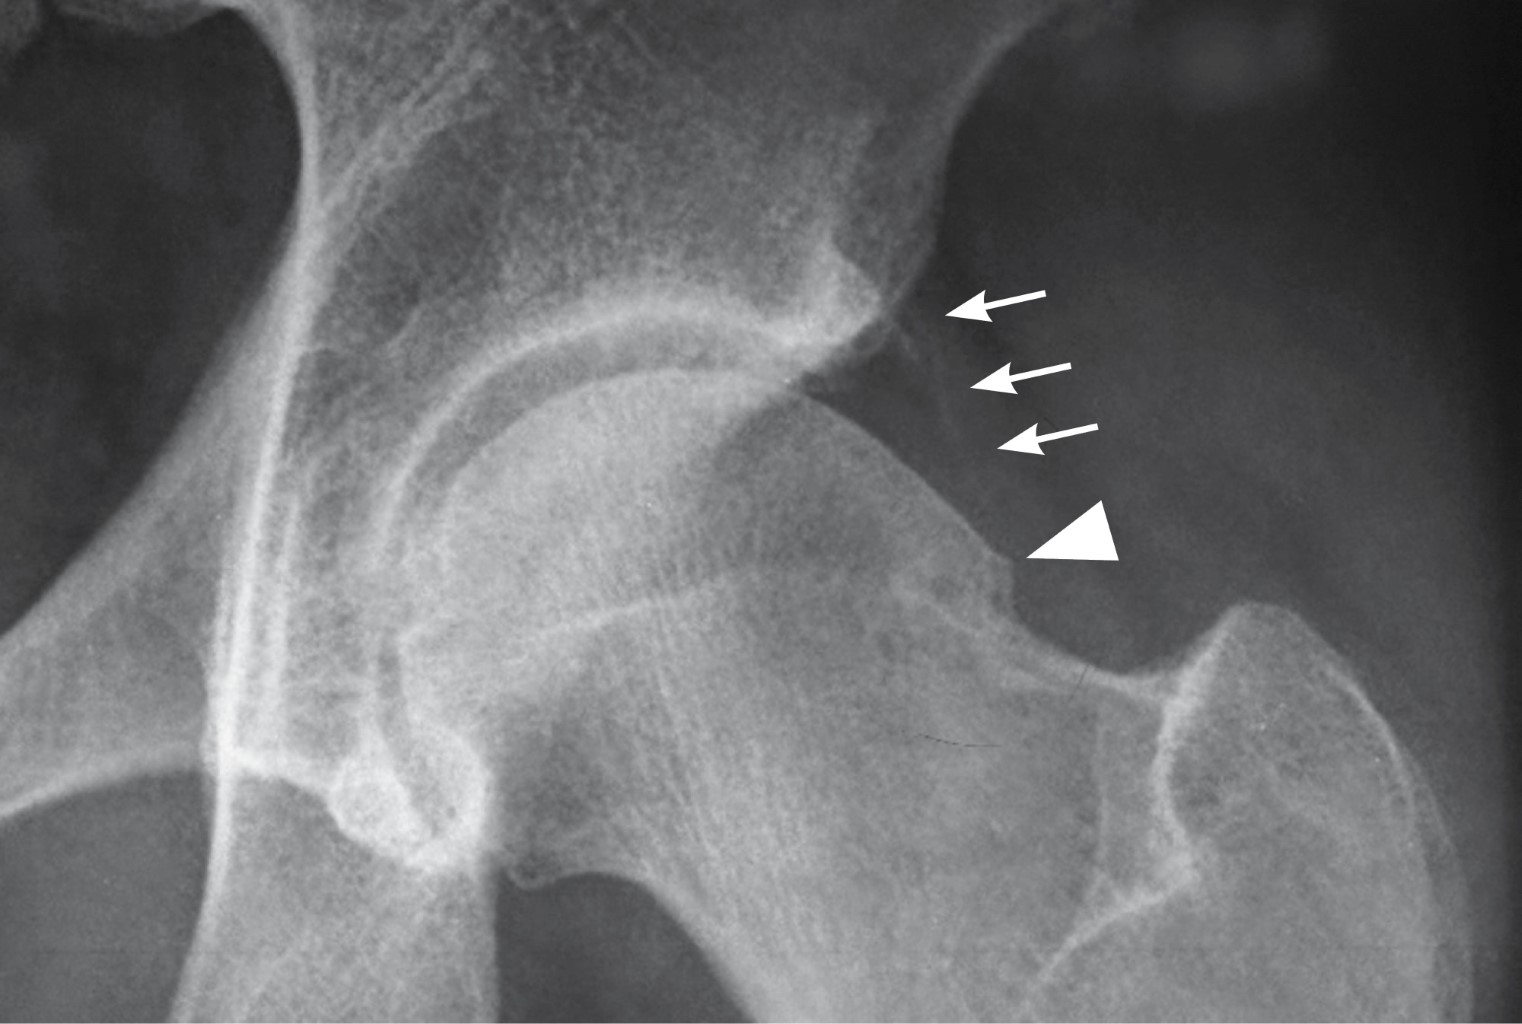

Masculino de 36 años de edad, profesionista, sin antecedentes de importancia, con dolor inguinal de un año de evolución, que se exacerba posterior a juego de balompié, obligándolo a suspender la actividad. A la exploración dirigida, postura y marcha sin alteraciones, dolor a la exploración de articulación coxofemoral durante la rotación interna y aducción con flexión de cadera a 90o, al igual que durante abducción con cadera en posición neutra. En radiografía anteroposterior de cadera se observa anormalidad de fémur izquierdo en la unión cabeza cuello, correspondiendo a pinzamiento femoroacetabular tipo leva (Figuras 1, 2 y 3).

El pinzamiento femoroacetabular tipo leva (FAI tipo CAM por sus siglas en inglés) (la leva es un elemento mecánico que está sujeto a un eje en un punto que es excéntrico a su centro geométrico) es una causa conocida de dolor inguinal que puede provocar osteoartritis de la cadera. Los pacientes que padecen esta afección son principalmente jóvenes que experimentan dolor inguinal durante los movimientos de rotación interna y aducción con la articulación coxofemoral en flexión de 90o; ocasionado por contacto anormal entre la unión cabeza-cuello femoral y el borde acetabular debido a anormalidad anatómica del fémur, ya que la morfología de la cabeza femoral no es esférica por alteración o anomalía del cuello femoral.1 Esta anormalidad se observa en 40% de los pacientes que desarrollan osteoartritis de cadera; puede ser secundaria a enfermedades del fémur proximal típicas de la infancia, incluidas secuelas de epifisiolistesis de la cabeza femoral, enfermedad de Legg-Calvé-Perthes, a infección de la articulación coxofemoral en la infancia y traumatismos de la articulación. Al ser una patología dinámica su desarrollo también está relacionado con actividad deportiva intensa. La prevalencia de la deformidad del choque femoroacetabular tipo leva es mayor en el género masculino.2 Su diagnóstico temprano resulta importante para establecer estrategias de tratamiento en pacientes con dolor de cadera preartrítico, la serie radiográfica de cadera al igual que la resonancia magnética y la tomografía con medición del ángulo alfa proporcionan las pautas de medición prequirúrgica.3 El pinzamiento femoroacetabular se puede tratar mediante procedimiento quirúrgico abierto o por artroscopia. Se informan complicaciones clínicamente relevantes en 4.8% de los pacientes con cirugía abierta y la tasa general de complicaciones asociadas con la artroscopia de cadera es discretamente menor (4%).4

Figura 1